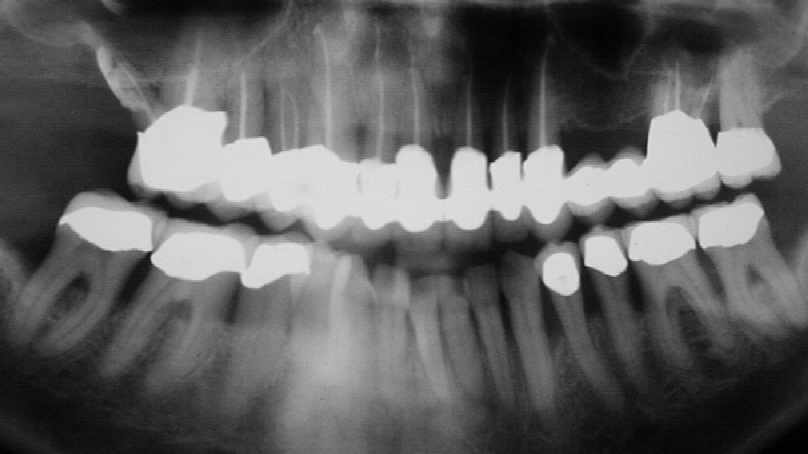

Unmittelbar nach prothetischer Versorgung im August 2002 (Klick!

Auffällig ist, dass sich der Erfolg der Maßnahme trotz der ausgesprochen ungünstigen Voraussetzungen eher in Zentimetern als in Millimetern messen lässt, wobei die Sondierungstiefen dem Röntgenbefund entsprechen. Dies, obwohl es sich eher um eine Verzweiflungstat unsererseits gehandelt hat, keine Membran benutzt wurde, lediglich Cerasorb ohne zusätzlichen Eigenknochen eingebracht wurde, es zur zweimaligen Nahtdehiszenz mit anschließender sekundärer Wundheilung kam, man die Caerasorb-Kügelchen längere Zeit klinisch freiliegend beobachten konnte.

Dieser Fall, der eindeutig Lindhes Kriterien entspricht, die zu dieser Meinungsänderung geführt haben, kann jedoch trotz seines ursprünglich sehr dramatischen Verlaufs nach dieser langen Periode des Sistierens jeglicher Parodontitissymptomatik in unseren Augen als ausgeheilt betrachtet werden. Wir sehen eigentlich nicht, warum diese Versorgung nicht zumindest die nächsten 10 Jahre ohne weiteren unphysiologischen Knochenverlust überdauern sollte. Ein anderer Verlauf würde uns aufgrund unserer Erfahrung bei vor langer Zeit sanierten Fällen ausgesprochen überraschen. Dies um so mehr, als das Problem im Bereich 14-15-16 offensichtlich beseitigt ist.